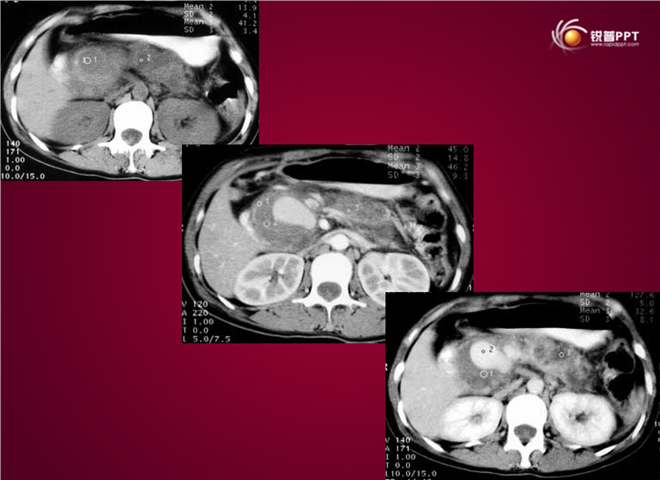

23_CT读片基础